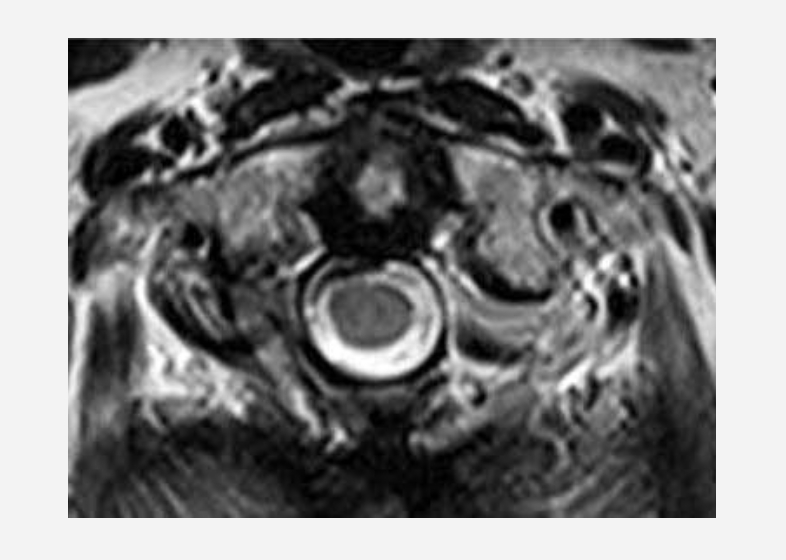

腫瘍が摘出され、脊髄の圧迫は消失している